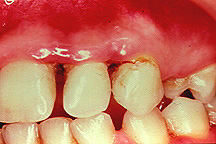

Parodontite moderate

dintii par alungiti datorita retractiei gingivale

pot apare abcese parodontale

halena

mobilitate dentara si diastemizare patologica

pungi parodontale de 4-6 mm

resorbtie osoasa